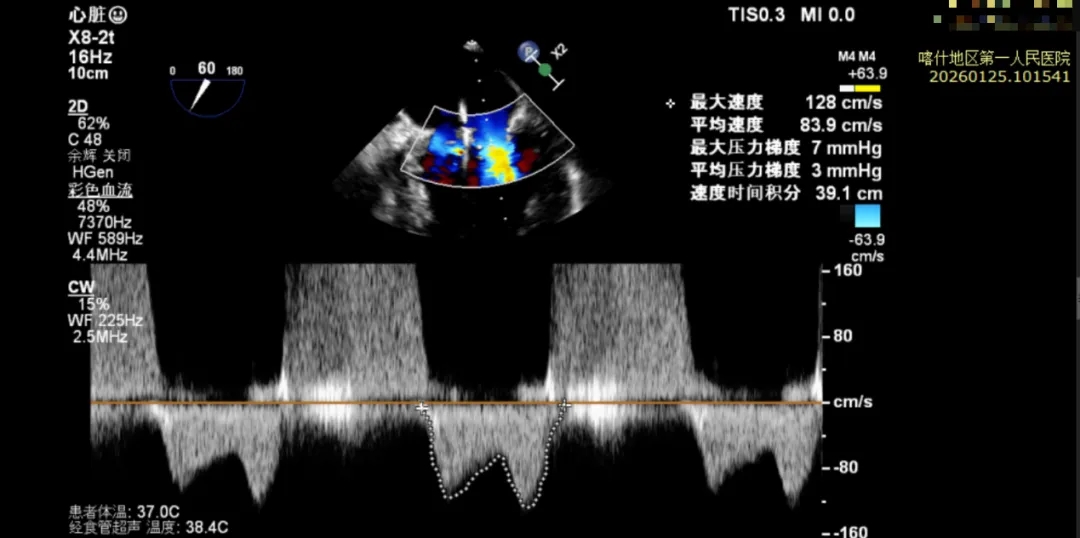

该例患者为DMR,脱垂区域较宽,术前制定手术策略:使用2把XTR先于患者外侧交界至1区部位进行钳夹。术中房间隔穿刺高度为4.0cm。成功穿刺后将SGC和XTR-CDS依次送入左心房,通过操控“M”旋钮调节SGC,使二尖瓣夹避开华法林脊,成功定位于2区正上方。在2区进行弹道测试成功后,进行Orientation调整。第一把于外侧交界区夹持,第二把于1区夹持,术中成功捕捞和夹持瓣叶后缓慢关紧夹臂,TEE检查见二尖瓣反流程度降低至1+,术后平均跨瓣压差3mmHg,手术顺利结束。

术后平均跨瓣压差3mmHg